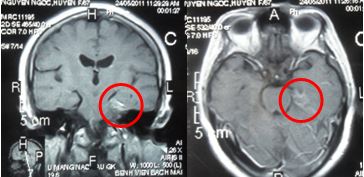

Hình 2: Sau điều trị xạ phẫu 6 tháng: u màng não còn rất nhỏ, giảm kích thước trên 80 %, bệnh nhân thuyên giảm triệu chứng tê mặt, thị lực mắt trái tốt hơn

Hình 3: Sau điều trị 10 tháng: u màng não còn rất nhỏ, bệnh nhân thỉnh thoảng đau nửa mặt trái.